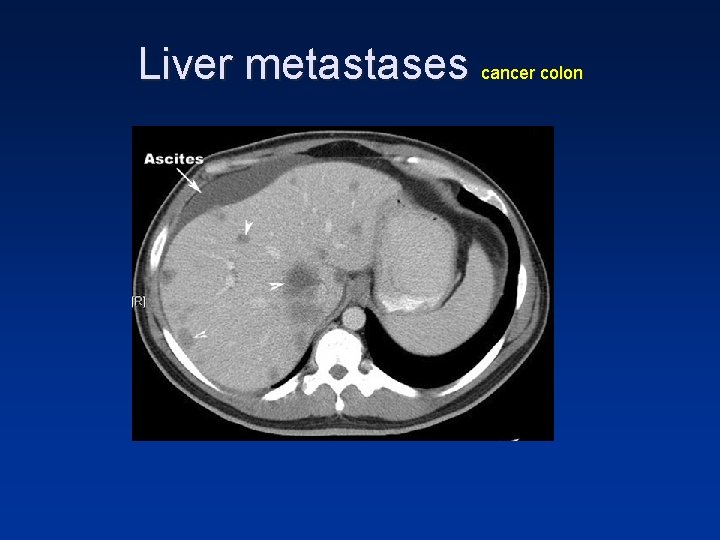

Liver metastases cancer colon

• Hypovascular metastases seen as hypodense lesions in late portal venous phase

• In the portal venous phase hypovascular tumors are detected when the normal liver parenchyma enhances maximally. • These hypovascular tumors will be visible as hypodense lesions in a relatively hyperdense liver.